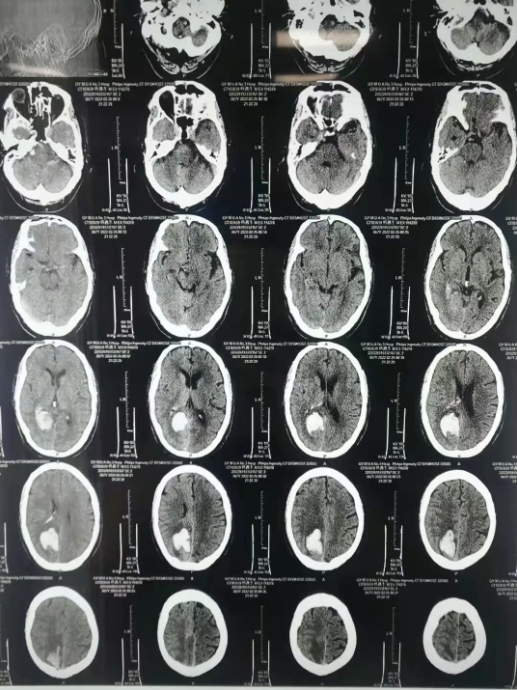

67岁的阳先生因“突发头痛伴视物模糊20+小时”收治于我院神经外科。入院后,头颅CT检查显示:右侧枕顶叶脑出血,破入脑室,周围脑水肿。需行内镜下右侧枕顶部开颅血肿清除术。

术后,血肿完全清除,阳先生神志清醒,双眼视力较前明显好转,下床自如行走。

(术后患者颅内血肿已清除)